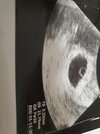

Będąc na urlopie w Polsce, nie wytrzymałam i poszłam prywatnie do lekarza. Na usg (teoretycznie 7+4) nadal nie widać płodu, jedynie "pierścionek". Czytałam że to pęcherzyk żółtkowy i że pare dni potem pojawia się zarodek. Lekarz stwierdził że płodu nie widać, powiedział że "coś tam puka", kazał iść na wizytę za tydzień a w rozpoznaniu wpisał podejrzenie pustego jaja płodowego.

Dziewczyny bety nie robiłam, ta moja lekarka stwierdziła że chce tę ciążę zobaczyć za 2 tygodnie i wtedy zrobimy badania (pierwsze zdjęcie 6+4). Kazała sie nie przejmować i przyjść za 2 tygodnie. Drugi lekarz ten w Polsce (drugie zdjęcie 7+4) powiedział że bety nie ma sensu, zebym poszła za tydzień tak jak mam wizytę umówioną, powtórzył też kilka razy że gdybym zaczęła krwawić to mam się zgłosić do lekarza, nie napawa to optymizmem..